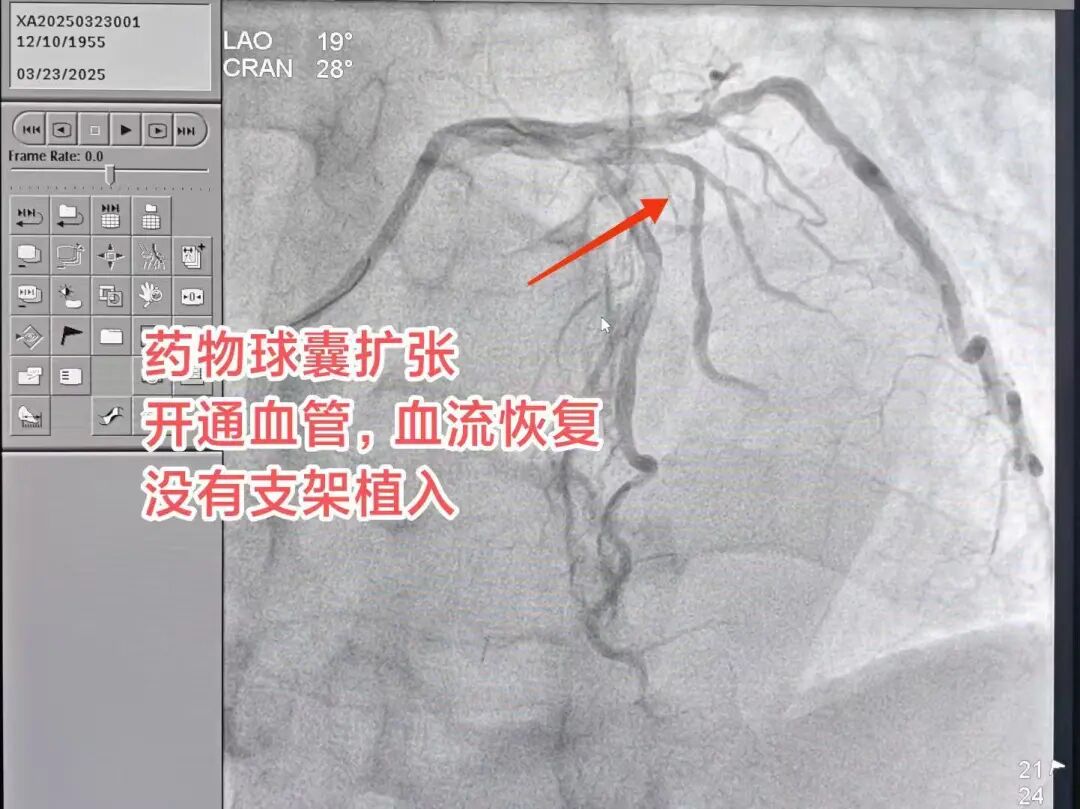

快速手术疏通血管

在导管室内,医疗团队迅速展开行动。他们首先进行冠脉造影,准确确定血管堵塞部位,然后通过介入治疗等方式,迅速开通堵塞的血管。整个过程紧张有序,体现了医疗团队的专业素养和高效协作。